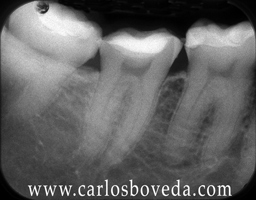

(para ver las rx a mayor tamaño haga click sobre ellas)